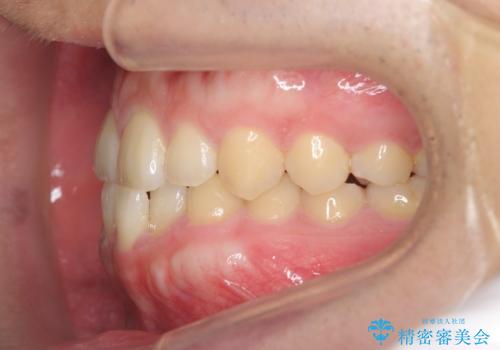

- 前歯の噛み合わせが反対になっていること、前歯の見た目の改善を希望され来院されました。

詳細な矯正検査の結果、顎の歪みが見られたため大きく歯を動かす治療ではなく前歯を主に並べることで前歯の前後関係を改善していきます。

前歯を主に動かす部分矯正であることからマウスピース矯正インビザラインによる治療を計画します。